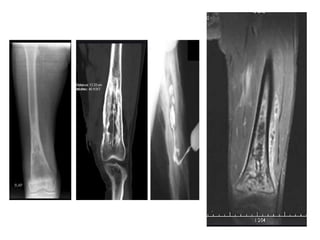

• Typical radiographic changes of OM

• Imaging studies demonstrating

sequestrum and contiguous soft

tissue infection